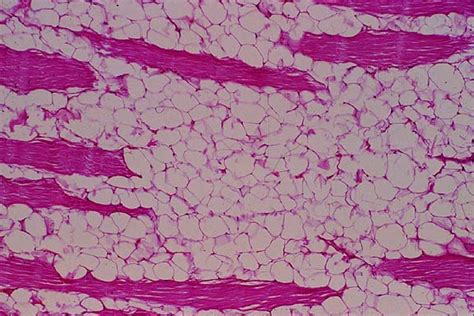

Липома. Липоматоз. Липобластома. Гибернома.

Липома патанатомия